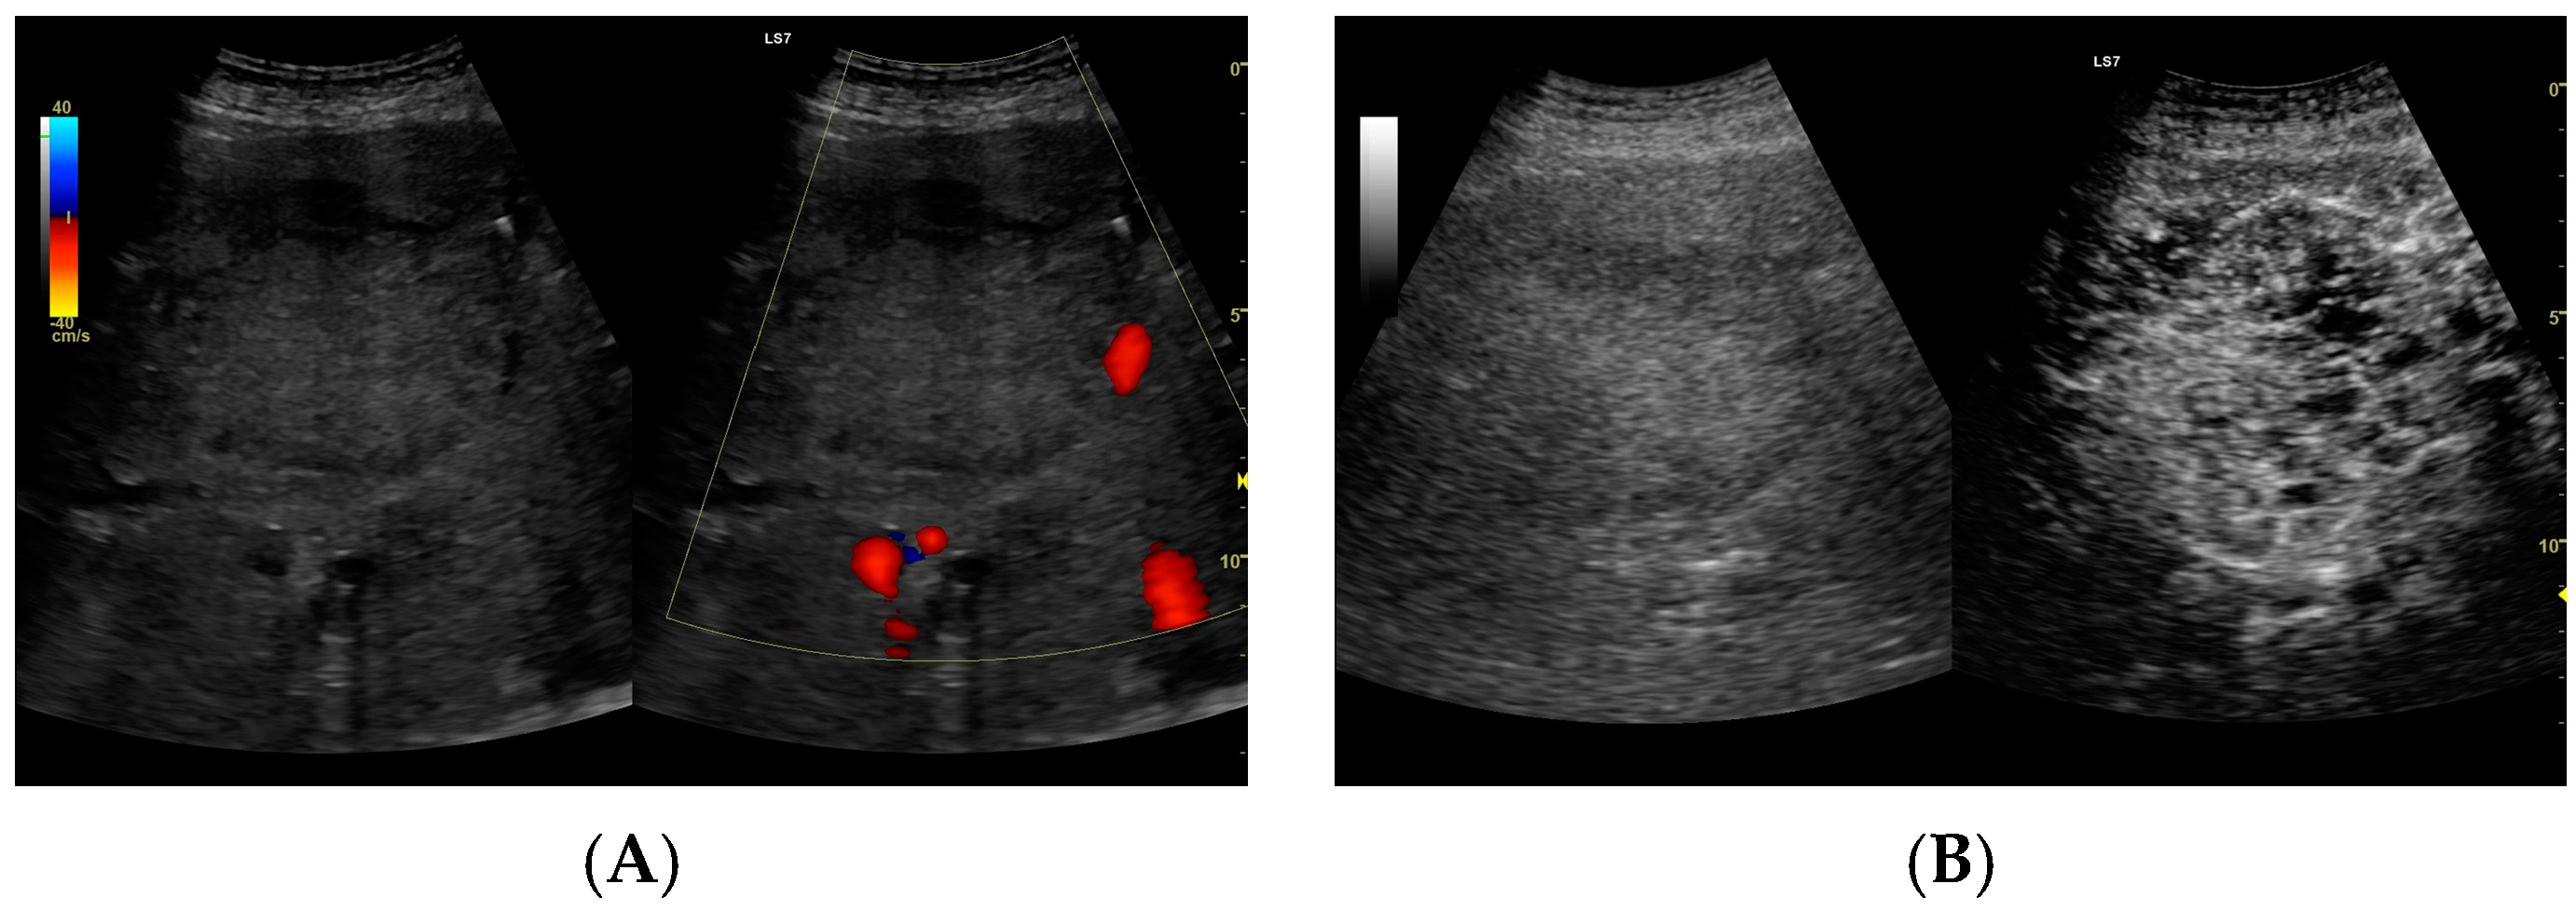

3.2.1. Arterial Phase

3.2.2. Early Venous Phase

3.2.3. Late Venous Phase